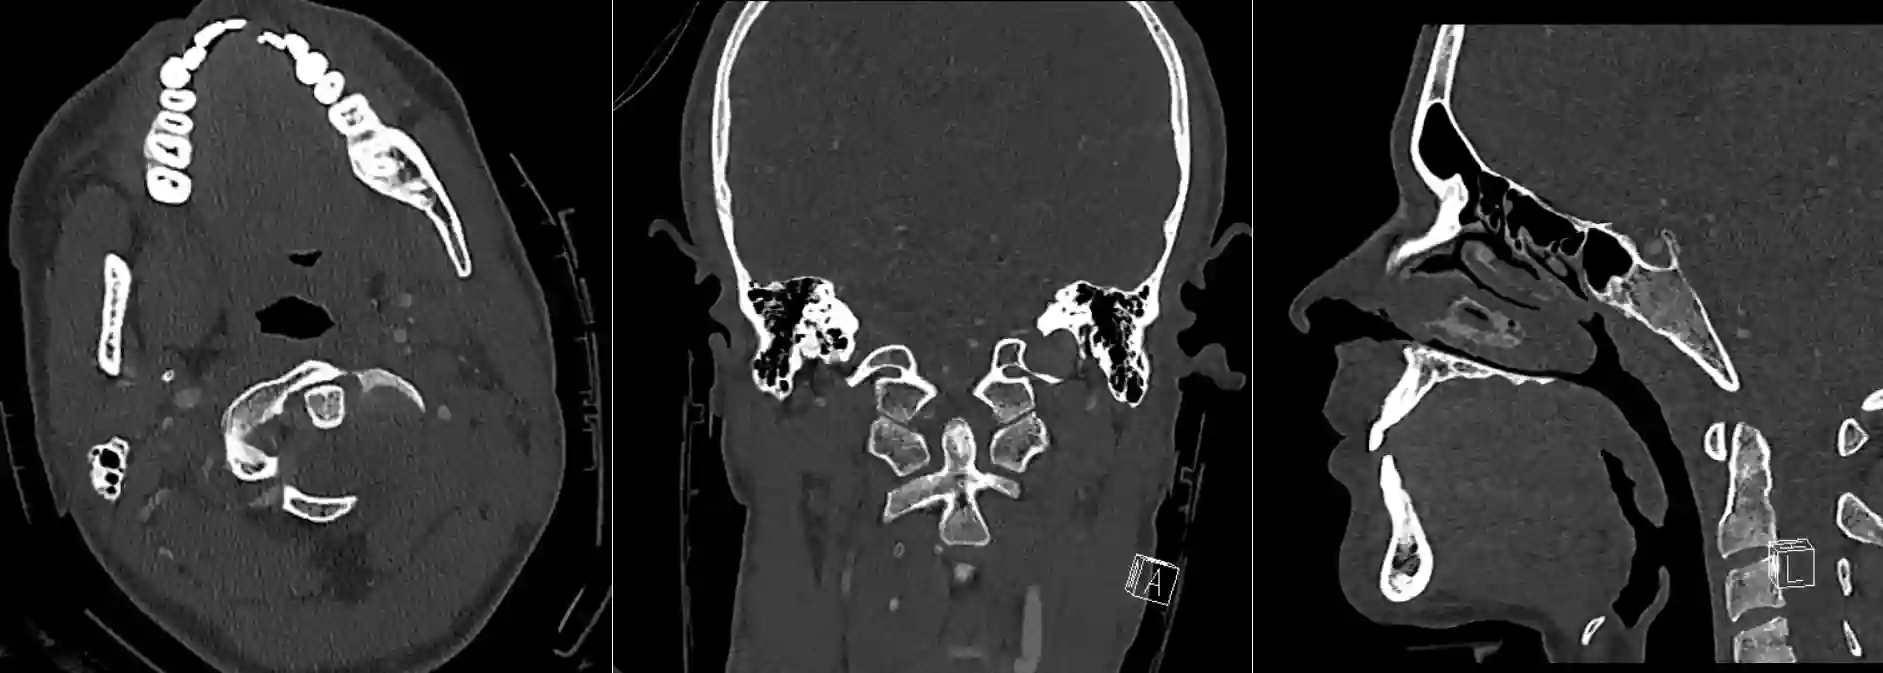

Dens axis im CT

Darstellung des Dens axis in drei verschiedenen Ebenen im CT.